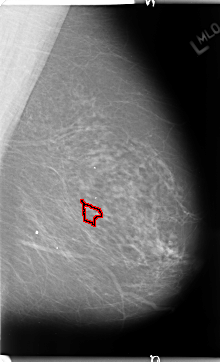

FILE: B_3126_1.RIGHT_MLO.OVERLAY

TOTAL_ABNORMALITIES 1

ABNORMALITY 1

LESION_TYPE MASS SHAPE ROUND MARGINS CIRCUMSCRIBED

ASSESSMENT 3

SUBTLETY 4

PATHOLOGY BENIGN

TOTAL_OUTLINES 1

BOUNDARY